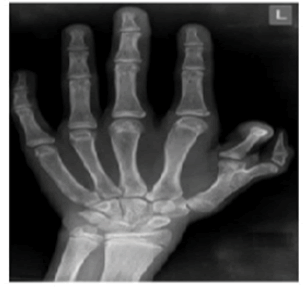

On general examination, he was conscious, oriented within normal mental functions. He was afebrile with a pulse was 120 bpm, blood pressure of 110/80 mm Hg, normal JVP, and normal height and weight for his age. Pallor, clubbing, cyanosis, pedal edema, icterus, and lymphadenopathy were absent. He has an absent thumb in the right hand, varus deformity of the right forearm, shortening of the right forearm with muscle agenesis, and polydactyly in the left hand (Figure 1A and Figure 1B). On cardiovascular examination, the apex beat was present in the left 5th intercostal space in the midclavicular line of heaving nature. Systolic thrill present in the left apical region. On auscultation, early to mid-systolic, a grade V murmur was present in the left second intercostal space at the sternal border. Loud P2 with wide fixed splits and opening snaps were present but no S3 and S4 were heard. The rest of the systemic examination was normal.

Haematological and biochemical tests including complete blood count, random plasma glucose, serum electrolytes, renal function test, and liver function, were within normal limits for age, but he had mild anaemia with haemoglobin of 10.7 gm. His left-hand X-ray revealed a supernumerary digit due to the presence of a bifid first metacarpal bone with an extra proximal phalanx (Figure 2). His X-ray right forearm revealed the absence of radius bone with an absent thumb and missing carpal bone (Figure 3). His ultrasound abdomen revealed the absence of the right kidney (Figure 4A and Figure 4B). The Electrocardiogram (ECG) showed biventricular hypertrophy, left atrial enlargement, incomplete RBBB with normal axis (78 degrees), and LVH strain pattern (Figure 5). Pre-procedure 2D ECHO revealed large secundum ASD along with significant right ventricular enlargement, pulmonary pressure of 35 mmHg systolic, and normal pulmonary venous drainage. Nearly 4 mm atrioventricular rim was deficient all other rims were adequate and no other structural abnormality was found (Figure 6A and Figure 6B).